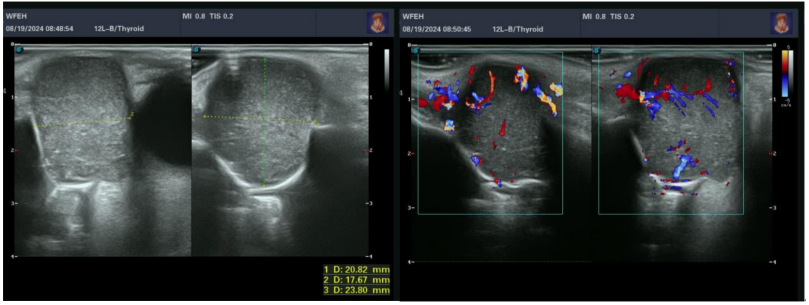

患者女,62岁,因左眼内眦肿胀1年于2024年8月19日入院。体格检查:左眼内眦部下方隆起,扪及直径约1.6 cm×1.8 cm的包块,质硬,轻微压痛,肿物自泪囊窝处向眶内延续。泪道冲洗:右眼上下泪小管内冲水通畅。左眼下泪小管冲水少量入咽,大部原路返流;上泪小管冲水全部原路反流,不能探入泪囊。眼眶彩色多普勒超声(彩超)检查(图1):左眼泪囊区可见低回声区,范围约2.4 cm×2.2 cm×1.8 cm,边界清,内回声欠均匀。彩色多普勒血流显像(color doppler flow imaging, CDFI):内可见树枝样较丰富血流信号。眼眶计算机断层扫描(computed tomography, CT)检查(图2):1)左侧泪囊鼻泪管及下鼻道内异常密度影,考虑肿瘤性病变可能大;2)左侧骨性鼻泪管增宽。眼眶磁共振成像(magnetic resonance imaging, MRI)检查(图3)示左侧泪囊鼻泪管及下鼻道内异常信号,考虑肿瘤性病变可能大。实验室检查结果未见明显异常。于2024年8月20日在全身麻醉下经皮肤切口联合鼻内镜入路行左眼眶泪道肿物切除术,先自内眦部肿物表面皮肤做切口,见肿物有完整致密薄膜,呈灰白色,向泪囊窝内延续;转至鼻内镜下,自泪颌缝前约6~7 mm纵向切开鼻黏膜向下切至下鼻甲黏膜,向后剥离鼻黏膜,暴露上颌骨额突及下鼻甲,使用咬骨钳及动力磨钻去除骨性鼻泪管内侧壁,见泪囊、鼻泪管膨大,将泪囊、鼻泪管连同鼻泪管口附近部分下鼻甲、下鼻道黏膜充分游离,其间见鼻泪管受挤压后鼻泪管口有不规则的灰白色软性颗粒样物质溢出;经内眦切口将肿物摘除。将鼻黏膜复位覆盖创面,可降解止血棉填塞固定鼻黏膜,分层缝合内眦切口。标本巨检:病变累及泪囊、鼻泪管全长,大小约为3.5 cm×2.5 cm×1.6 cm,外壁呈灰白色,有较厚的包膜结构,局部切开可见内含大量白色质软胶冻状的不规则颗粒样、乳头样结构;病理诊断(图4):(左眼泪囊部)上皮源性肿瘤,囊性结构,衬覆柱状上皮、鳞状样上皮,伴有乳头状结构,可见少量黏液细胞。CK7(部分+)、CK5/6(+)、S-100(少量+)、P63(+)、SOX10(少量+)、Ki-67阳性细胞数约2%、PAS染色(少量+)。结合组织学形态及免疫组化结果,符合泪囊导管囊性扩张伴鳞状细胞化生,伴乳头状瘤形成,伴少量黏液细胞化生。患者术后3周时复诊见鼻黏膜基本愈合,出院后曾到耳鼻喉科会诊建议观察随诊;2024年11月2日第二次复诊见左侧鼻腔黏膜愈合好,未见复发改变(图5),患者除溢泪症状,无其他不适。下一步诊疗计划:定期复诊,术后6个月以上无复发可考虑行使用鼻黏膜再造泪道的结膜-鼻腔吻合置管术。

图 1 一例泪道乳头状瘤的彩超结果

Figure 1 Color doppler ultrasonography results of a case of lacrimal papilloma

左眼泪囊区可见低回声区,范围约2.4 cm×2.2 cm×1.8 cm,边界清,内回声欠均匀。彩色多普勒血流显像:内可见树枝样较丰富血流信号。A hypoechoic area is visible in the left lacrimal sac region, measuring approximately 2.4 cm × 2.2 cm × 1.8 cm, with clear borders and uneven internal echoes. Color Doppler flow imaging reveals a rich, branching pattern of blood flow signals within the area.